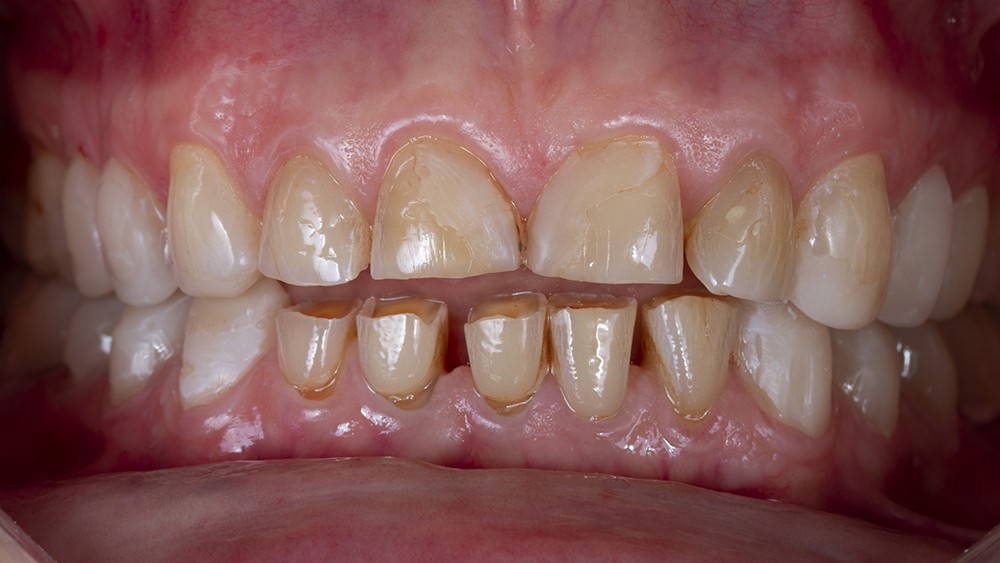

Le calage postérieur obtenu assure l’augmentation de la DVO et entraîne très souvent une béance antérieure avec une perte du guidage antérieur (fig. 8). Le traitement du groupe incisivo-canin est alors nécessaire.

La forme clinique des restaurations d’usage dépend de l’étendue de la perte tissulaire. Lorsque cette dernière est modérée, la réalisation de facettes vestibulaires permet le rallongement des bords libres usés dans le prolongement du rehaussement postérieur.

Dans les cas d’usure des faces palatines, la restauration du guide antérieur suppose une reconstruction grâce à la technique 3-step ou par des facettes en céramique dites à 360°. Dans cette dernière option, les faces palatines usées ne nécessitent qu’un congé fixant la limite prothétique, maximisant ainsi la préservation tissulaire et optimisant le collage à venir.